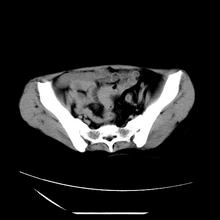

女性,41岁,发现左腹部包块3年,现行ct检查,检查前做过静脉肾盂造影。

左侧低密度区是脂肪密度,中间可见条索状软组织样密度影,现主要想知道左肾前下缘圆形软组织样密度影,内见低密度水样密度影,这是什么?

脾脏增大,左肾后方脂肪增多,脊柱前方脂肪增多,左肾窦脂肪增多,左肾变形,双肾积水以左侧为著,左肾内侧及上方见环形软组织肿物影,内部低密度区,考虑1盆腹腔/腹膜后及左肾窦脂肪增多症2左肾内侧病灶可能为左肾上腺病灶,可能为脂肪增多的原凶

1)考虑左肾替代性脂肪瘤病;不排除左肾错构瘤。2)双肾积水。

肾窦脂肪瘤病及肾替代性脂肪瘤病被认为是脂肪增殖程度不同的一种疾病。正常情况下肾窦内有少量脂肪组织充填,在某种情况下肾实质会发生萎缩,而以肾窦、肾门为中心脂肪或(和)纤维组织可出现增殖,当增殖局限在肾窦、肾门区时称为肾窦脂肪瘤,若同时部分或全部取代了萎缩破坏的肾实质时称为肾替代性脂肪瘤病。

发病机理有2种学说,大部分人认为是由于某些具有破坏性的肾脏疾病,如肾结石并感染、肾结核等造成肾破坏、萎缩,继发了大量的脂肪组织增殖;另一部分则认为肾脏慢性炎症可刺激脂肪组织的增殖,肾萎缩是继发的。

ct典型表现为以肾窦肾门为中心大量弥漫性脂肪积聚,鹿角状结石及萎缩的肾实质。合并肾周感染时,肾轮廓不清,周围有粘连性改变。

诊断rsl的必备条件是肾窦、肾门的脂肪组织增生和肾实质的萎缩,而且本例因为ivp后扫描不好判断有无肾结石但可能性较小;另外,占位效应显著,脾后缘都受压了,肾门以下肾实质残缺,支持肾脏错构瘤.